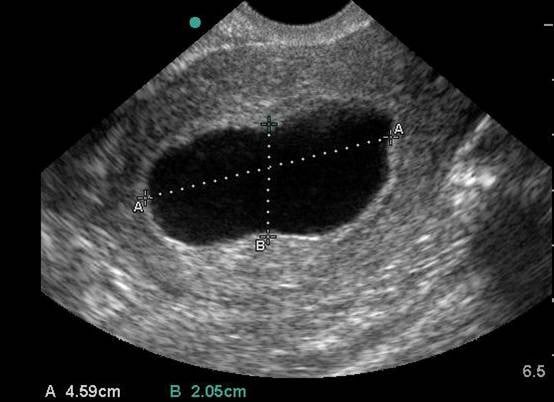

- Dating can be achieved by obtaining crown rump length when fetal pole becomes visible and then biparietal diameter when fetal skull becomes evident at the end of the first trimester.1 (Illustration 10, 11)

- Illustration 10. Transabdominal transverse view of 10-week fetus with crown rump length measurement.